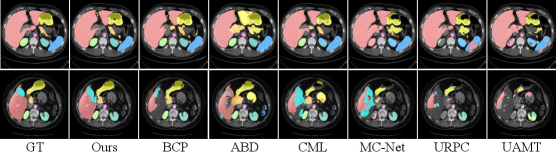

3.2 Comparison with State-of-the-art Methods

We compare the proposed method with several state-of-the-art (SoTA) semi-supervised medical image segmentation methods, including UA-MT [yu2019uncertainty], SASSNet [li2020shape], DTC [luo2021semi], URPC [luo2021efficient], MC-Net [wu2021semi], SS-Net [wu2022exploring], MCF [wang2023mcf], BCP [bai2023bidirectional], CML [wu2024cross], and ABD [chi2024adaptive] under 5% and 10% labeled settings, as summarized in Tables 1 and 2.

As shown in Table 1, our UCAD consistently outperforms all competitors on the ACDC dataset under both label ratios. With 5% labeled data, it achieves 88.63% DSC and 0.49 ASD, outperforming previous SoTA methods and demonstrating effective use of unlabeled data. When the label ratio increases to 10%, our method further improves to 89.93% DSC and 0.57 ASD, showing stable and robust consistency learning. Similarly, on the Synapse dataset (Table 2), our approach achieves the best results under both 5% and 10% labeled settings, with DSC gains of 4.82% and 2.24% over ABD. The significant improvement on complex multi-organ CT scans highlights the advantage of our contour-aware mixing in preserving anatomical structures and refining boundaries.